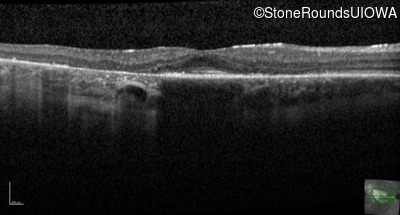

Age at visit: 30 years

This 30 year old man first noticed poor vision in dim light when he was five years old. His visual acuity began to fall in his early 20's.